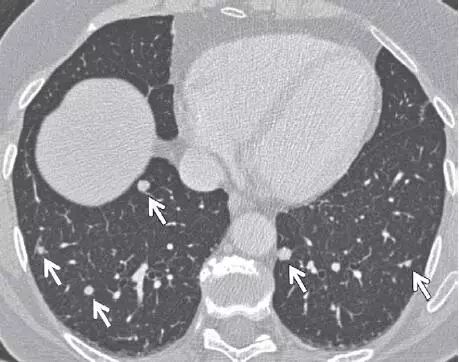

可是不甘心啊,儿子还没结婚,夫妻之间很有感情,还是拿出毕生的积蓄给她治,上了靶向治疗,药费非常贵 ,花了十多万 ,也就半年时间,最后包了个车回老家料理后事。后面聊天时我问起这个保安师傅,他说夫妻感情几十年,你不给治于心不忍啊!唯一后悔的是没重视体检,因为他自己每年保安公司都是有体检的,觉得老婆身体底子好,不会有什么事。像女性肺癌一般腺癌比较多见,如果能在早期比如结节阶段切除,预后可就大不相同了。

肺结节